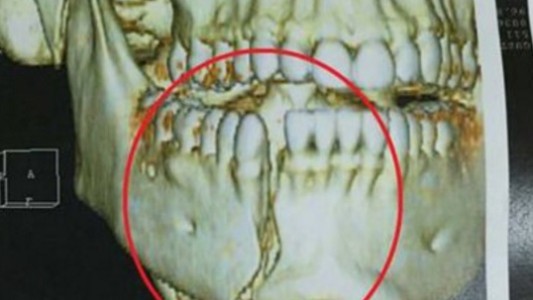

Brasil: así quedó la mandíbula del policía herido por rugbiers argentinos